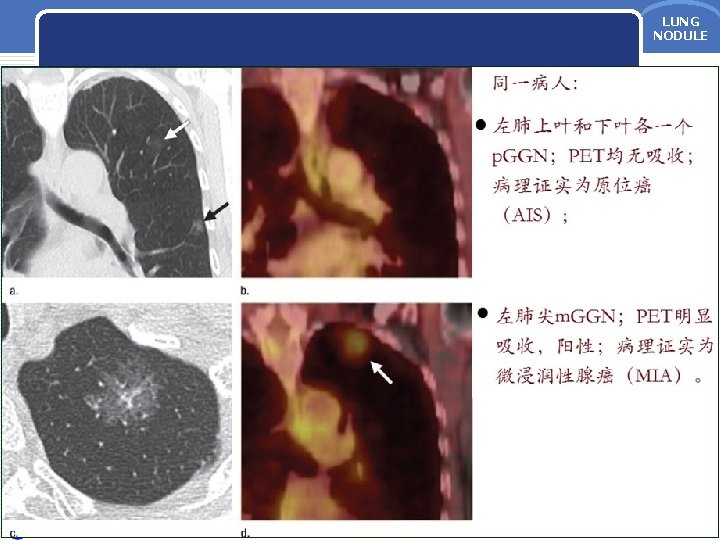

原位腺癌(AIS) LUNG NODULE v 原位腺癌(AIS)多为非粘液性,HRCT上表现为: • p. GGN,密度较AAH略高; • 直径一般> 5 mm; • 少部分AIS因肺泡壁塌陷而呈m.

原位腺癌(AIS) LUNG NODULE v 原位腺癌(AIS)多为非粘液性,HRCT上表现为: • p. GGN,密度较AAH略高; • 直径一般> 5 mm; • 少部分AIS因肺泡壁塌陷而呈m. GGN。 v AIS的预后:很好,手术切除后5年生存率达 100%。 Lee HY, et al. Am J Roentgenol 2014; 202: W 224 -33. Myrna CB, et al. J Thorac Imaging 2012; 27: 240 -6. Travis WD, et al. J Thorac Oncol 2011; 6: 244 -85. Yang ZG, et al. Am J Roentgenol 2001; 175: 1399 -1407. 四川大学华西医院 22